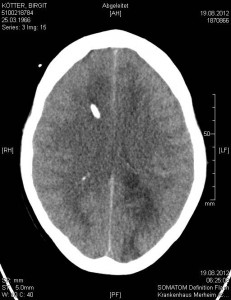

Nach dem multiplen Infarkt vom 19.08.2012 sind diese Strukturen nicht mehr erkennbar: